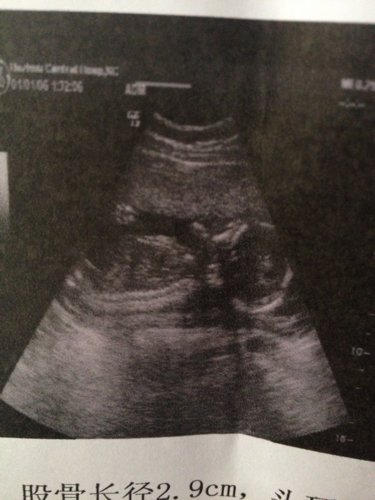

胎儿双顶径4.3cm,股骨长2.9cm,胎心率152 羊水深度3.3cm!胎儿是否正常 能知 道是男宝还是女宝吗 点击展开 匿名用户 2013-07-29 12:36 为您推荐: 其他回答 您好,胎儿的B超显示宝宝4个多月,发育还好,现在宝宝生殖器已经分化完全,但是B超上看不出是男女,没有照到那个部位,这张是宝宝头部和身子的图像。 罗lili 2013-07-29 12:39 相关问题 我怀孕5个月了,双顶径4 8cm,股骨长3 3cm,胎心率136次/分,羊水深度3 7cm,请问正常吗? 孕35+3,双顶径7 7㎝,股骨长6 3cm,胎心率138 /分,羊水深度5 6㎝,正常吗?胎儿大 怀孕七个半月双顶径约8 0cm股骨长约5 8cm胎儿心率139/分羊水最大深度约60cm 这样正常吗?宝宝大概有多大